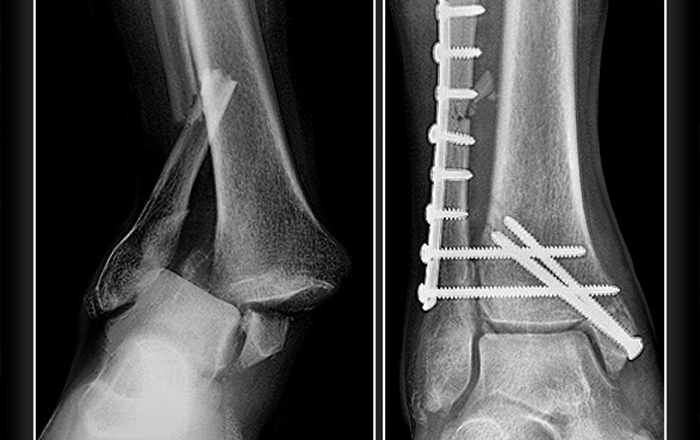

• Kapalı redüksiyon ve perkütan fiksasyon

• Açık redüksiyon ve internal fiksasyon

• Plaka-vit sistemleri